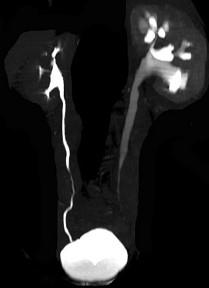

问题 男,59岁,反复尿频尿急尿痛4年余,尿常规检查:红细胞(+),白细胞(++),CT扫描如图示,下列说法正确的是 ( )

选项 A.左侧输尿管中下段输尿管管壁增厚,管腔狭窄 B.左侧侧输尿管上段扩张 C.考虑为输尿管结核 D.考虑为慢性输尿管炎 E.考虑为输尿管移行细胞癌

答案 ABD